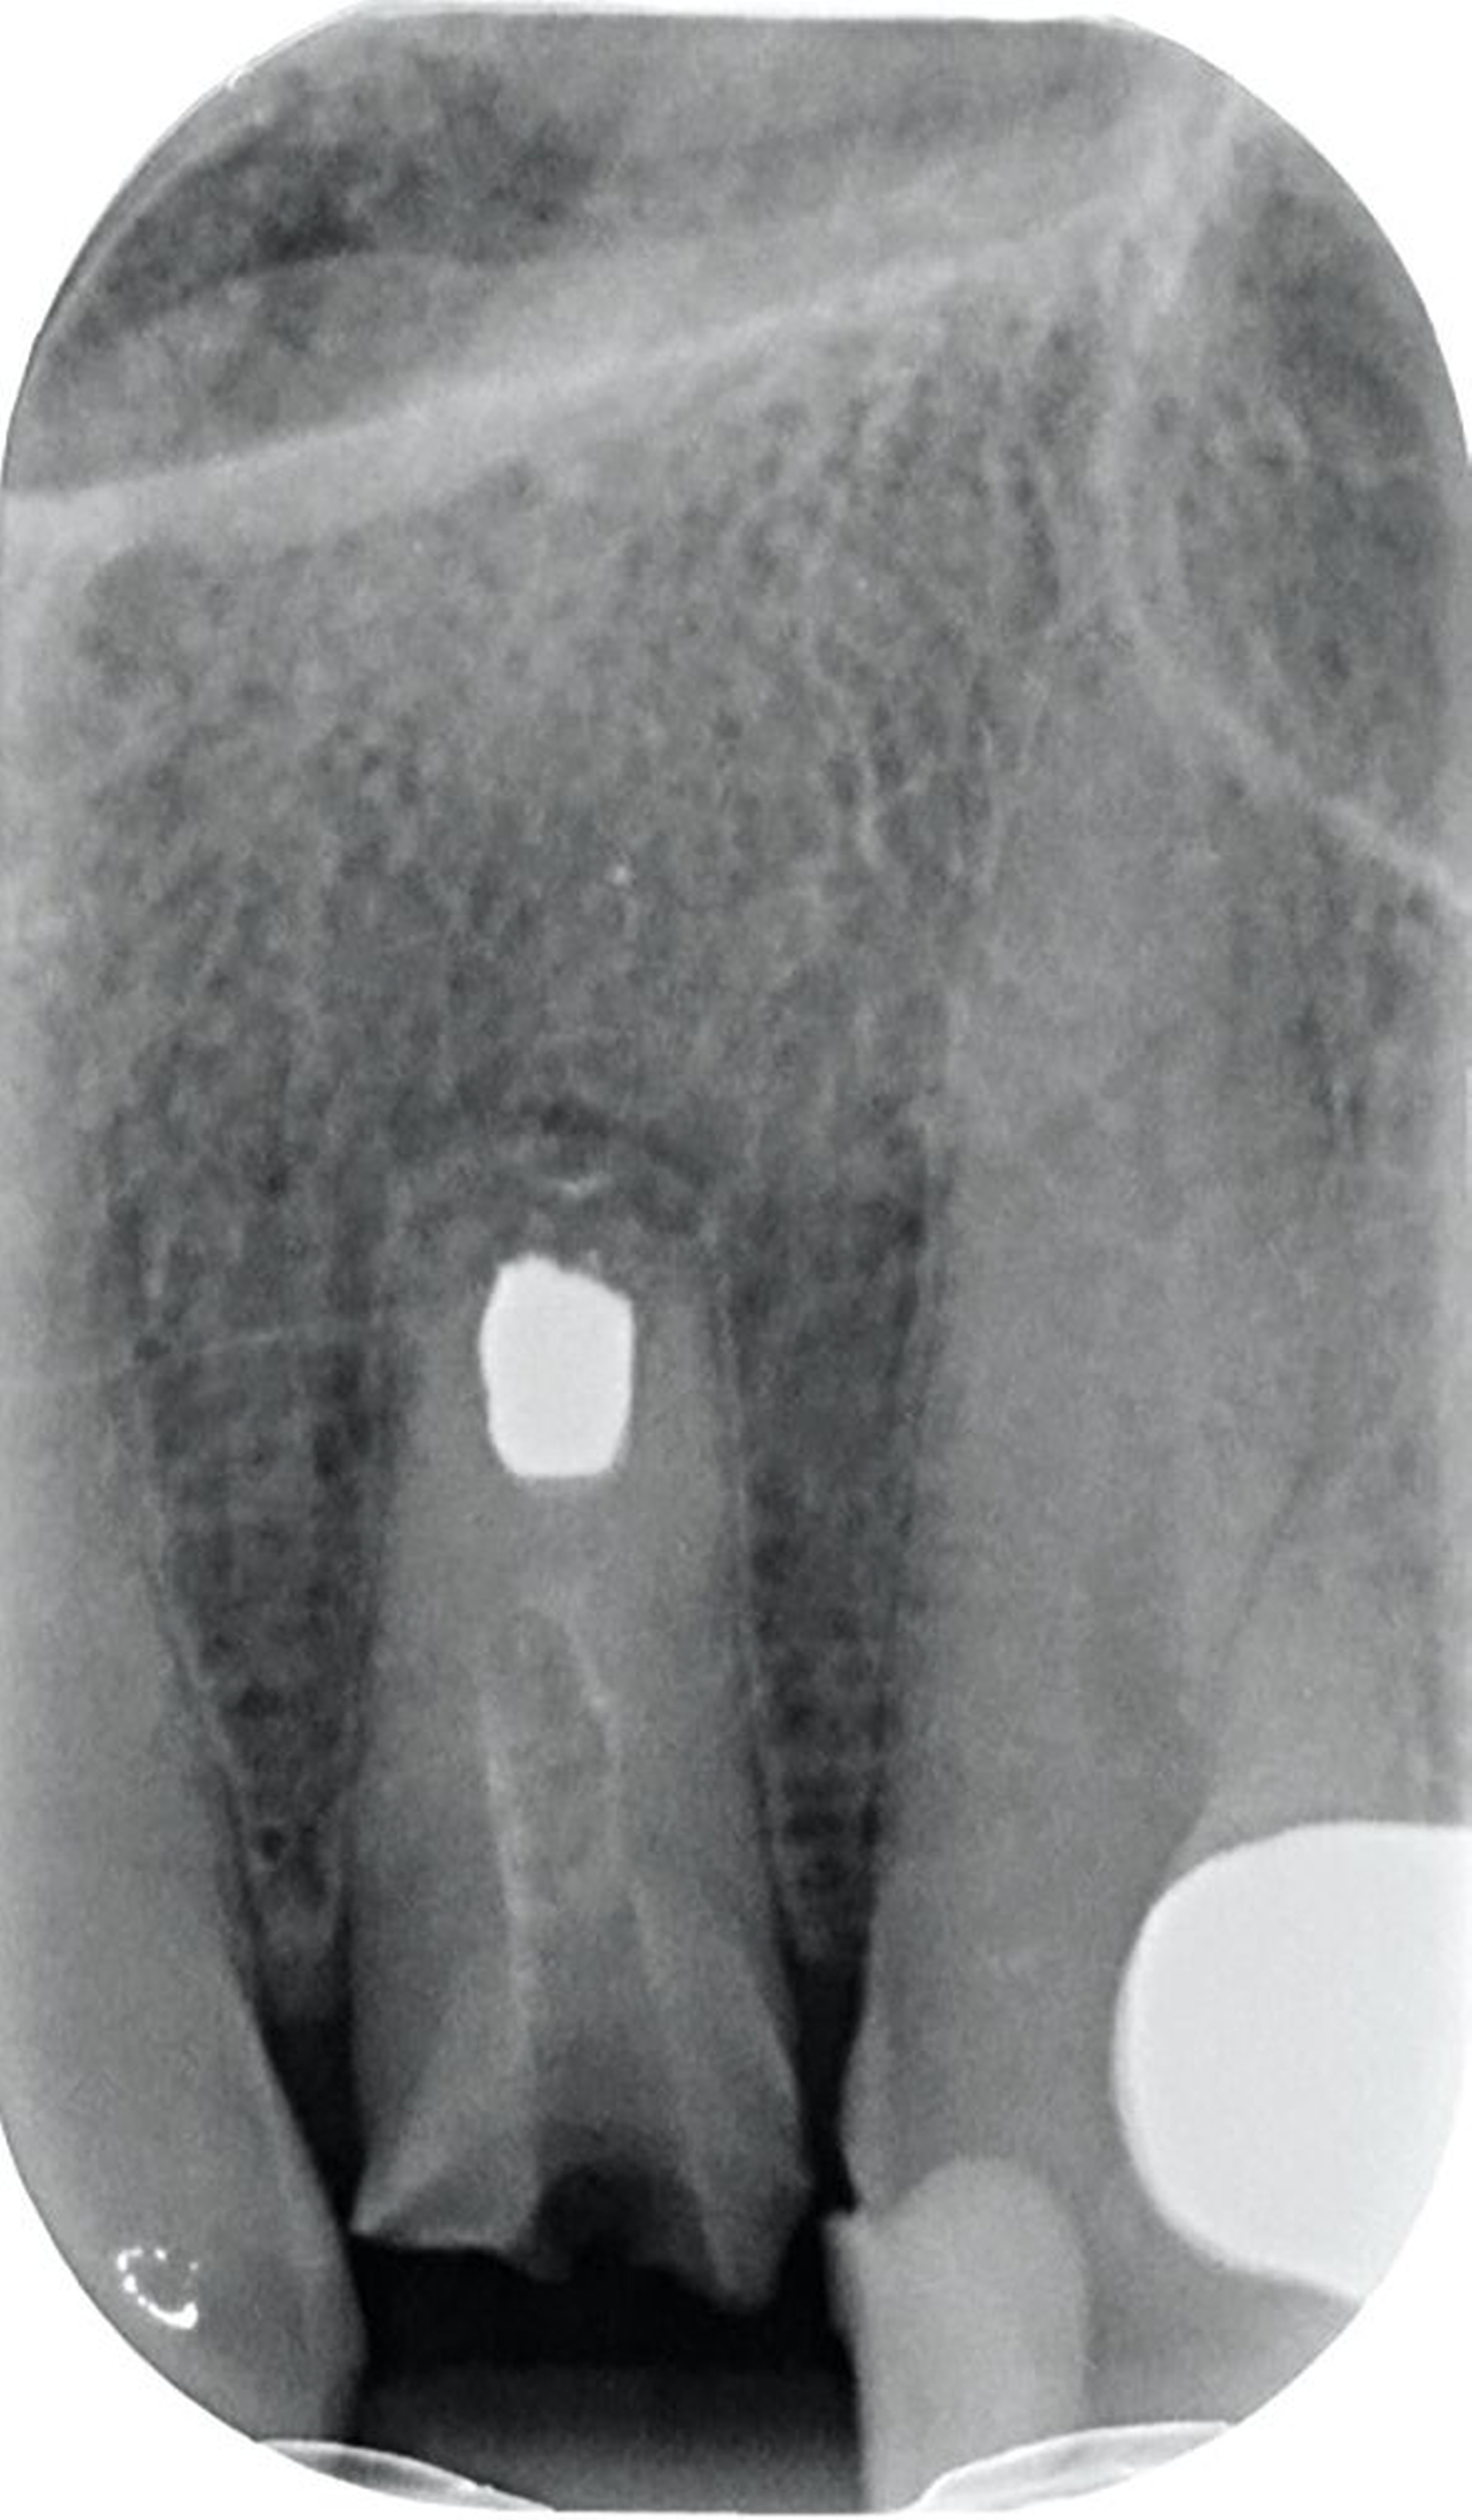

Vor 25 Jahren hatte der Patient ein Frontzahntrauma an Zahn 22 erlitten, der daraufhin mit einer Wurzelspitzenresektion und einer retrograden Amalgamfüllung versorgt worden war (Abbildung 3a). Dabei war die Zahnkrone mit einer keramisch verblendeten Stiftkrone aus Nichtedelmetall rekonstruiert worden, die nun aufgrund von Sekundärkaries insuffizient und gelockert war, jedoch keine Beschwerden verursachte. Klinisch wies der Zahn eine sehr kurze klinische Krone ohne ausreichendes Ferruledesign auf (Abbildung 5a) [Naumann et al., 2018a; Naumann et al., 2018b]. Neben dem Verdacht auf einen obliterierten mittleren Wurzelkanalabschnitt gab es röntgenologisch keinen Hinweis auf apikale Osteolysen oder parodontale Auffälligkeiten (Abbildung 3b). Der Patient entschied sich trotz des erhöhten Zahnhartsubstanzdefekts für den Zahnerhalt durch einen adhäsiv verankerten Kompositaufbau.

Für die restaurative Therapie von Zahn 22 wurde die alte Stiftkrone entfernt und die Stiftbohrung an die neue Indikation angepasst (Abbildungen 5a und 5b). Die Zahnkrone wurde dabei in drei Phasen wiederhergestellt: adhäsives Zementieren eines konfektionierten Glasfaserstifts, Stumpfaufbau und Modellation einer direkten Kompositkrone mit Silikonschlüssel, Frontzahnmatrize für komplexe Situationen und Schneepflugtechnik (Abbildungen 5c bis 5e) [Urkande et al., 2023; Amaro et al., 2021; Frese, 2020; Mannocci et al., 2002; Dimitrouli et al., 2011; Opdam et al., 2003]. Im Röntgenkontrollbild zeigt sich ein suffizienter Stiftaufbau (Abbildung 6).